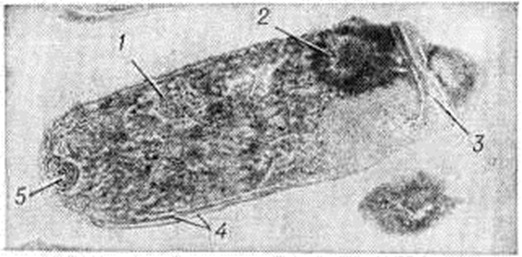

ДифтерияДифтерия (греческий diphthera кожа, плёнка) — острая инфекционная болезнь с воздушно-капельным путём передачи возбудителя, характеризующаяся воспалительным процессом в зеве, гортани, трахее, реже в других органах с образованием фибринозных налётов и явлениями интоксикации. Чаще поражает детей. Оглавление Патогенез и патологическая анатомия ИсторияКлассическое описание и объединение различных форм болезни сделал Бретонно (P. F. Bretonneau) в 1826 год; он дал ей название дифтерит. А. Труссо предложил ныне общепринятое название дифтерия. В 1883—1884 годы Клебс (T. A. E. Klebs) и Ф. Леффлер открыли и выделили в чистом виде возбудителя болезни. В 1892—1894 годы Э. Беринг и одновременно Э. Ру и Я. Ю. Бардах получили противодифтерийную сыворотку. Введение в практику серотерапии явилось важнейшей вехой в истории Дифтерия. В 1902 год С. К. Дзержговский доказал возможность активной иммунизации человека против Дифтерия В 1913 год Э. Беринг разработал метод активной иммунизации смесью токсина и антитоксина. Г. Рамон в 1923 год предложил иммунизацию дифтерийным анатоксином. В разработку и усовершенствование противодифтерийных прививок большой вклад внёс П. Ф. Здродовский. ЭтиологияВозбудитель Дифтерия — Corynebacterium diphtheriae — относится к роду Corynebacterium (Lehmann, Neumann, 1896), группе коринеформных бактерий (Bergey’s Manual of Determinative Bacteriology, 1974); морфологически представляет собой полиморфные тонкие, слегка изогнутые палочки 0,5 × × 1,0—3,0—5,0 микрометров (встречаются ветвящиеся, сегментированные и кокковидные формы — цветной рисунок 1). При электронно-микроскопическом изучении (рисунок 1) видна трёхслойная клеточная стенка, у многих штаммов есть микрокапсула (Е. И. Нехотенова с соавторами, 1963; И. С. Барбан, 1964). В цитоплазме имеются нуклеоид, внутрицитоплазматические мембраны — мезосомы, вакуоли, а также как необязательный компонент — скопления полифосфата, так называемый зерна волютина или Бабеша—Эрнста. При окраске фиксированных бактерий Дифтерия анилиновыми красителями зерна окрашиваются метахроматически по отношению к цитоплазме; скопления нуклеиновых кислот в клетках придают им полосатость. Бактерии Дифтерия грамположительны. Благодаря делению клеток в виде излома и расщепления они нередко располагаются под углом друг к другу. Жгутиков не имеют, спор^ не образуют. Морфологически Cor. diphtheriae бывает неотличима от многих штаммов других коринебактерий, встречающихся на коже и слизистых оболочках человека (так называемый дифтероидов), и для определения видов внутри рода требуется изучение комплекса культуральных и биохимический признаков. По устойчивости к воздействию факторов окружающей среды бактерии Дифтерия не отличаются от неспорообразующих патогенных бактерий. Возбудитель Дифтерия весьма чувствителен к действию многих антибиотиков — пенициллина, тетрациклина, эритромицина. Однако в носоглотке больных и носителей, несмотря на лечение этими препаратами, бактерии Дифтерия могут находиться длительное время. |

Дифтерийная интоксикация характеризуется поражением нервной, сердечно-сосудистой систем, надпочечников и почек. С большим постоянством выявляются изменения в узлах симпатической части высшая нервная система, где, помимо сосудистых расстройств, обнаруживается более или менее выраженная дегенерация ганглиозных клеток. Поражение периферических нервов проявляется множественным токсическим невритом (смотри полный свод знаний Невриты). Отмечается повреждение нервных оболочек, и прежде всего миелиновой оболочки — деструктивные изменения в ней нередко достигают полного распада и гибели миелина (рисунок 2). В миелиновой оболочке происходит пролиферация клеточных ядер. В меньшей степени изменяются осевые цилиндры; обычно лишь часть их подвергается деформации и распаду.